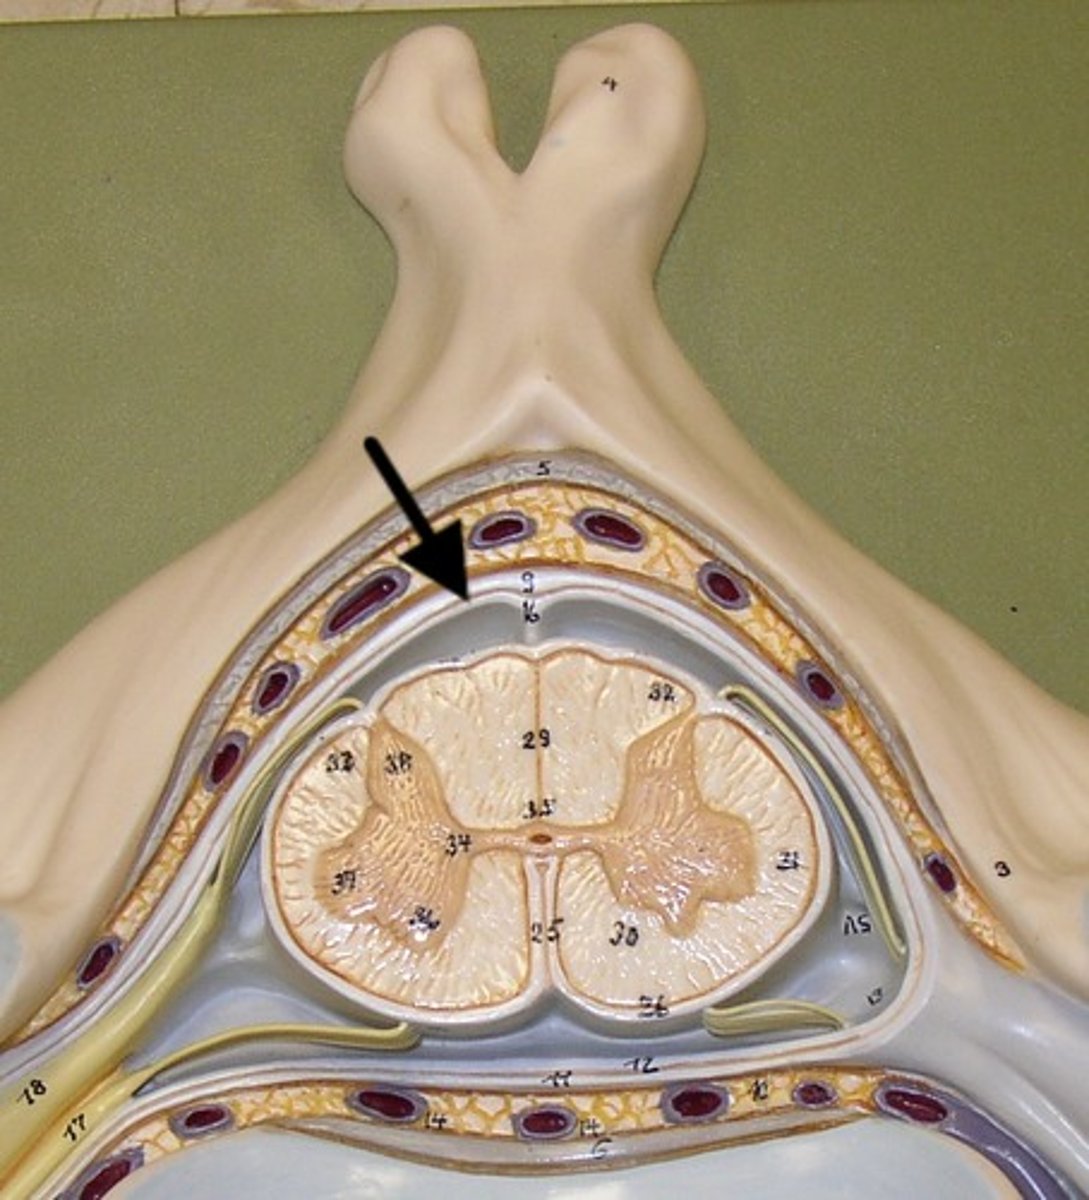

lateral Aperture

fourth ventricle

Dura Mater

Arachnoid Mater

Subarachnoid

Pia Mater